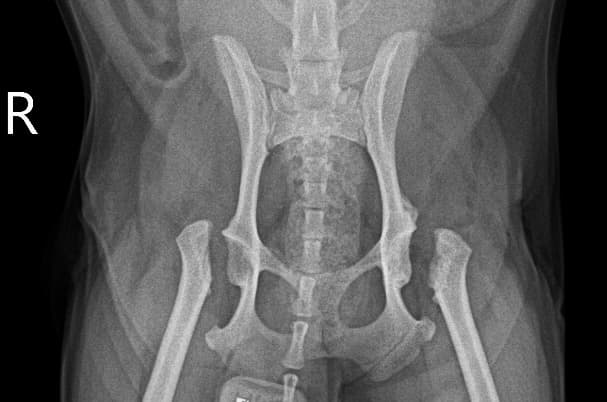

동탄 1 신도시 최초 Aquilion CX/128 slice CT를 동물병원에 도입하였습니다. 최고 사양 CT 모델 Aquilion CX/128 slice를 활용하여 0.5 mm의 얇은 128개의 단면 영상을 신속히 획득 할 수 있어 마취 시간을 단축시킬 수 있습니다. 또한, 128 슬라이스의 고화질의 CT 영상을 통해 영상 왜곡을 최소화하고 X-ray에서는 확인하기 힘든 5 mm 이하의 미세 병변도 확인이 가능하여 정확한 진단을 할 수 있습니다. 심화 진단이 필요한 경우, 조영제 인젝터를 통한 동맥기 촬영으로 종양 유래 확인, 간 질환 진단, 심혈관계 진단이 용이합니다. 저희 동탄시티동물의료센터에서는 본원 환자뿐 아니라 1차 동물 병원과의 CT 촬영 의뢰 시스템을 통해서 원활한 협진이 가능하도록 최선을 다하고 있습니다.

0164 채널 CT 촬영을 통해서 신속하게 고화질 영상을 얻어, 종양 유래 확인 및 전이 평가, 간문맥단락증(PSS), 선천적 뼈 기형과 같은 심화된 진단을 할 수 있습니다.

64채널 검출기 시스템 128

슬라이스 이미징 능력

고속 스캔 및 높은 해상도 제공

저선량 기술 적용으로 환자 방사선 노출 감소

흉복부, 골격계 전반의 선명하고 우수한 영상을 저선량으로 촬영이 가능